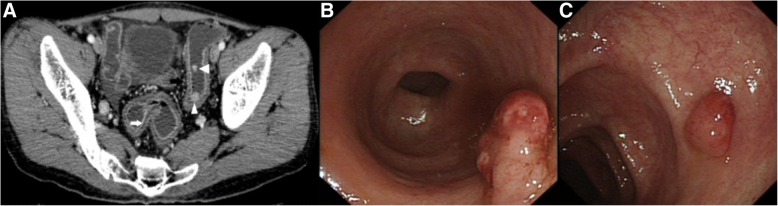

Fig. 4.

Axial (a) and CTE of UC demonstrated two enhancing mucosal nodules in sigmoid colon (white arrowheads). Colonoscopy-guided biopsy (b and c) in sigmoid colon confirmed them both to be pseudopolyps

Of the total 46 cases, bowel wall thickening was seen in 43 cases (Figs. 1, 2, 3, 4). Mural hyperenhancement was observed in 45 cases (Figs. 1, 2, 3, 4). Mural stratification was present in 21 cases (Figs. 1, 2, 4). Mucosal bubbles were present in 30 cases (Fig. 1). Loss of haustration was identified in 28 cases (Fig. 3). Mesenteric hyperemia was present in 23 cases (Figs. 2, 3, 4). Perirectal stranding was seen in 14 cases (Fig. 2). Lymph node enlargement was present in 19 cases. Intestinal pseudopolyps were identified in five patients (Fig. 4). Luminal narrowing was seen in 12 cases (Fig. 3).